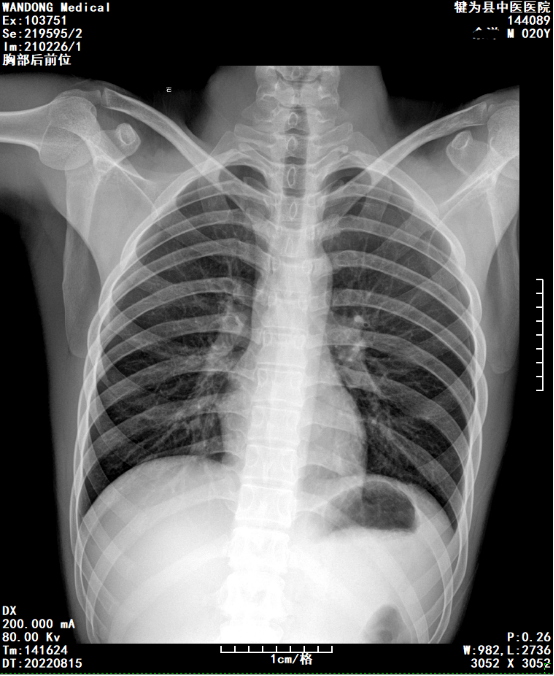

X线片

这是一张胸部正位片,图像一般分为几个区,右上为机器及图片信息,左上为患者及检查信息,下方为显示视野。

图中标记的A、P、R、L为方位,分别为前后右左;刻度尺比例,1分隔为1CM,可自行对比量病变大小。

DX代表X线数字摄影;

下面是扫描参数,200mA是电流,根据时间可知道做检查所受的剂量;80KV是电压,临床中技术老师会根据病人的具体情况调节电压大小;DT为检查时间。

WL代表窗宽、窗位,可简单理解为图像明暗及对比度;3052X3052代表该幅图像的像素,乘积数越高代表图像的清晰度越高,由平板探测器的性能决定。